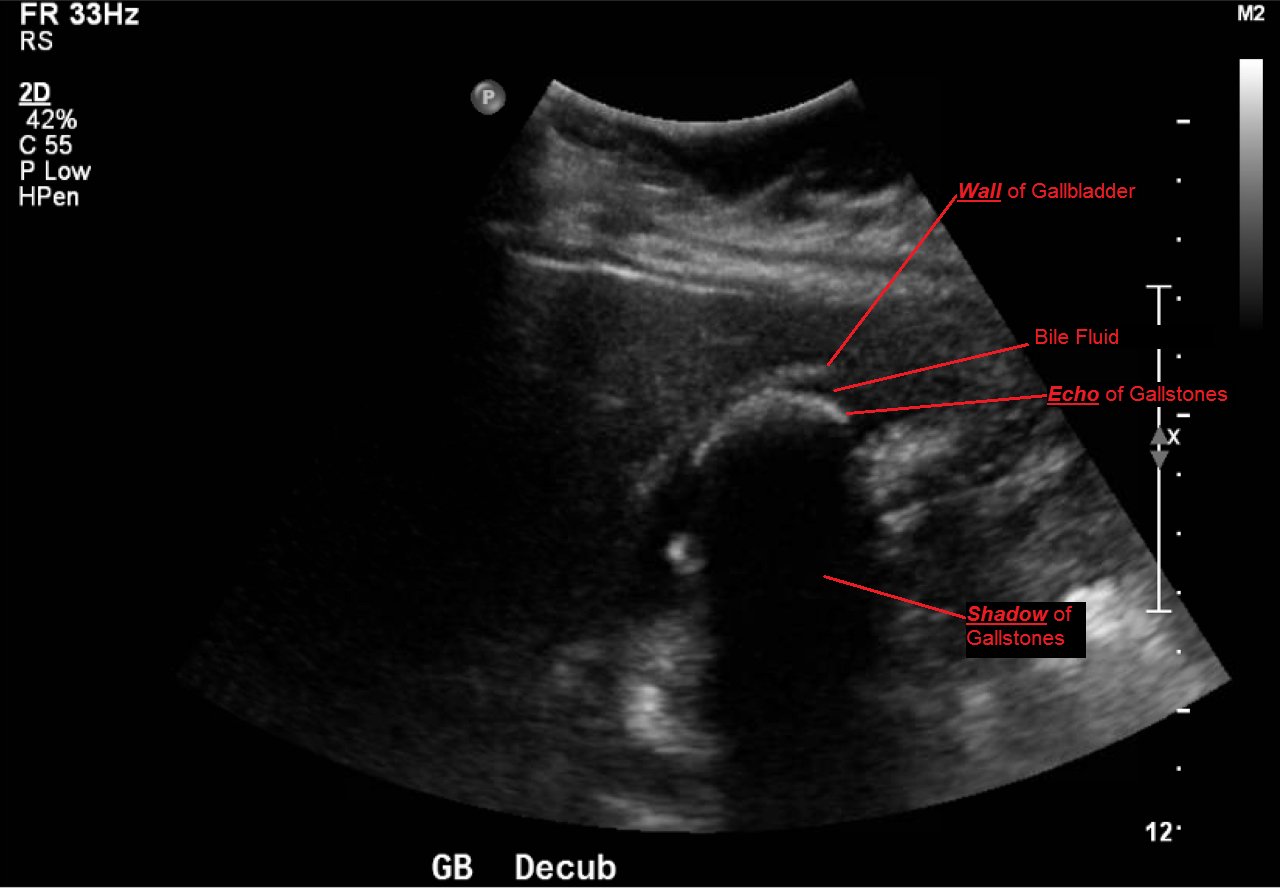

Cholelithiasis: WES Sign

Abdominal ultrasound showed the classic presentation of the Wall-Echo-Shadow (WES) sign. The superficial aspect of the gallbladder wall is represented by a hyperechogenic curve. Below this, bile fluid is represented by hypoechogenicity. Underneath the bile fluid is the echo of the dense border created by the collection of gallstones, represented by a hyperechogenic curve. Due to the high density of the gallstones, nothing deeper can be visualized (including other gallstones or the far end of the gallbladder); this is the shadow.

The WES sign, first described in the early 1980s, is a clear way of identifying cholelithiasis when the condition has progressed to fill the entire lumen of the gallbladder.1 In this case, the lumen of the gallbladder looks hypoechogenic relative to the surrounding tissue, much like an empty gallbladder. This is due to the border of the dense stones opposing the near wall of the gallbladder casting a shadow over everything distal to the stones. These key visualization techniques decrease non-visualization of chronic cholelithiasis.2,3,4 In most cases, WES sign is sufficient to diagnose cholelithiasis. Of note, “porcelain gallbladder” or collapsed duodenum can have the potential produce similar ultrasonographic findings.4,5